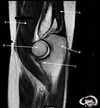

11

Q

What is letter A?

A

ANTERIOR LABRUM

How well did you know this?

1

Not at all

2

3

4

5